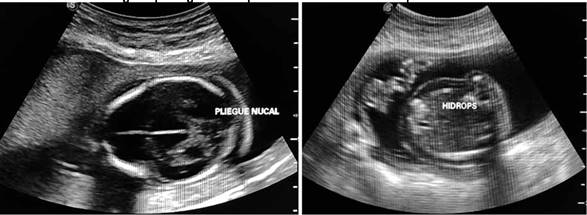

Se realiza interrupción del embarazo vía vaginal, mediante inducción usando análogos de prostaglandina E1. Al momento del nacimiento se evidencio feto de sexo masculino con un peso de 470 g. Se corroboró la presencia de higroma quístico, sumado a un edema generalizado (hidrops) y la presencia de onfalocele (Figura 3).

FIGURA 3. Hidrops Fetal, Feto obtenido mediante inducción.